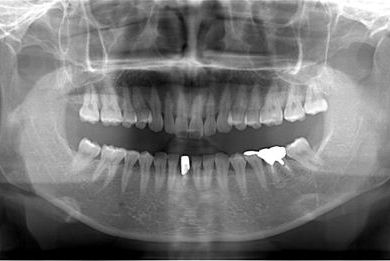

性別/年齢 女性 / 37歳

主訴 歯の差し歯が少しぐらつく。歯ぐきが違和感を感じる。

治療方針 抜歯と同時にインプラントを埋入し、治療期間を短縮する。

治療内容 インプラント1本(抜歯即日スピードインプラント)、メタルボンドセラミック1本

治療部位

1

治療前

• 治療前